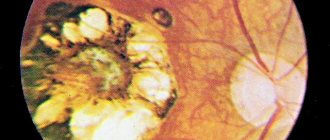

Токсоплазмозный хориоретинит

Смысл древнегреческих корней, из которых образован термин «хориоретинит», заключается в следующем. Хориоидея – сеть